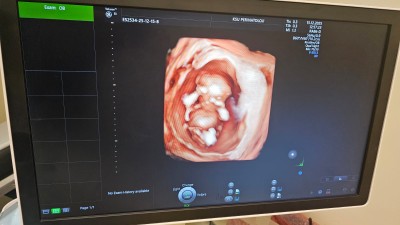

cinsiyet tahmini yapabilecek olan var mı

Gebelik haftası 13+3